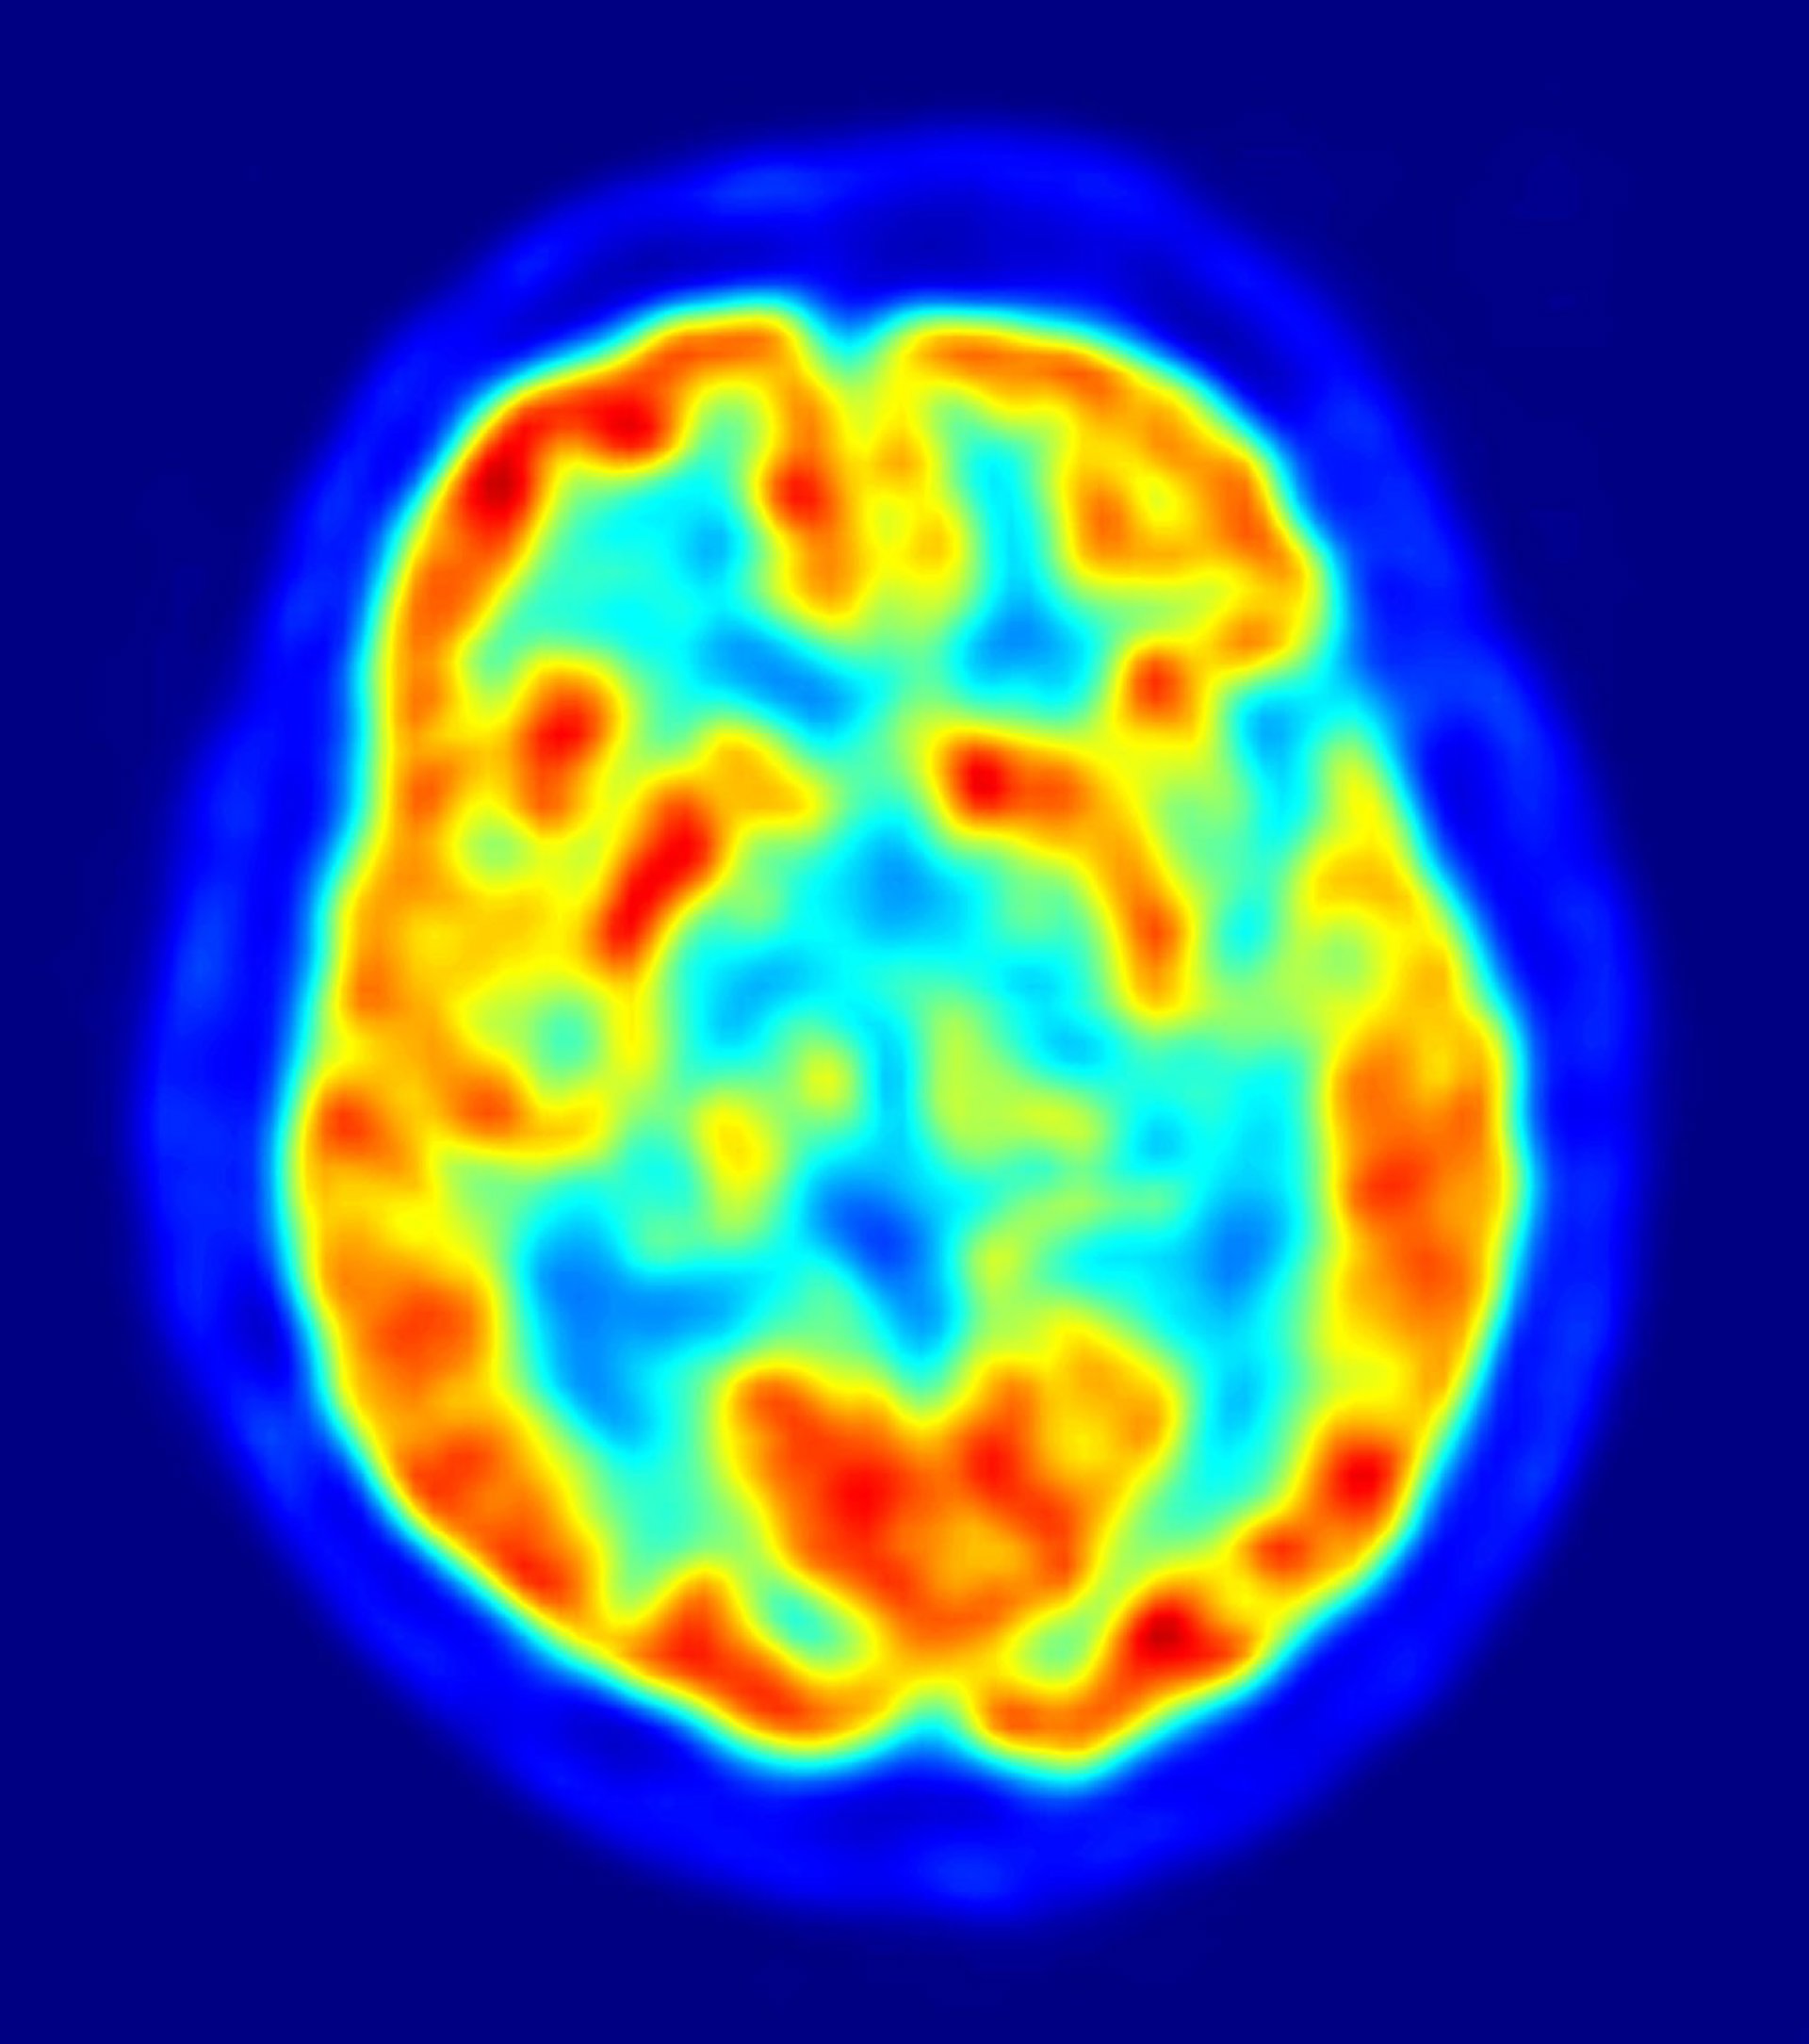

Los compuestos eliminados son unos péptidos llamados beta-amiloides, como proteínas, pero más cortos en longitud. Cuando estos péptidos beta-amiloides se acumulan en cantidades excesivas en el cerebro, pueden formar placas características de la enfermedad de Alzheimer.

Los resultados sugieren que jnk3 podría ser una nueva diana para tratar la enfermedad de Alzheimer. Por el momento, algunos medicamentos pueden retardar la progresión de la enfermedad, pero no hay cura. La enfermedad de Alzheimer afecta a más de 5 millones de estadounidenses y su causa se desconoce. Aunque los científicos no han determinado todavía si los péptidos beta-amiloides presentes en las placas causan Alzheimer, o son una consecuencia de la enfermedad, la presencia de las placas está ligada a una disminución cognitiva progresiva.